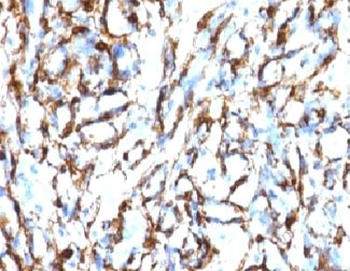

IHC: Formalin-fixed, paraffin-embedded Leiomyosarcoma stained with Smooth Muscle Actin antibody (clone SPM332).